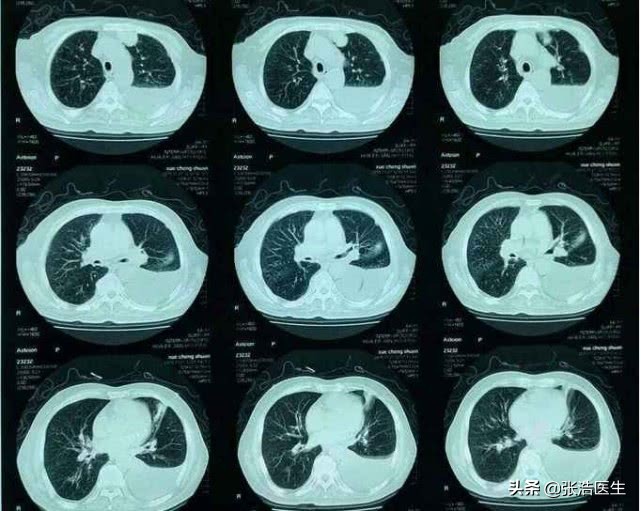

呼吸困难属于呼吸系统的症状,所以常见于呼吸系统的疾病,但是大部分的呼吸系统疾病多多少少都会伴有咳嗽的症状,所以有时候是食管、胸腔疾病,挤压到肺和气管等,也同样导致呼吸困难,如较多的胸腔积液,就会出现呼吸的困难。